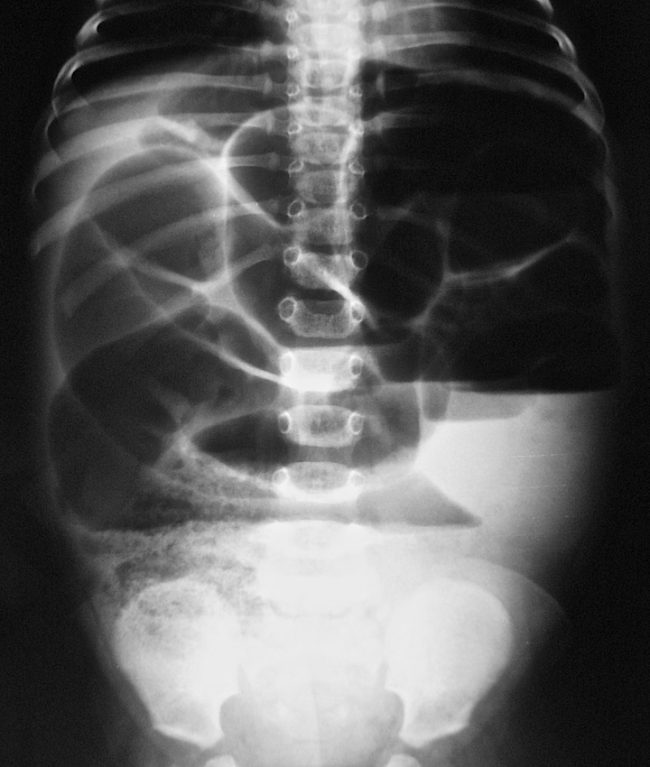

Нормы обзорной рентгенографии брюшной полости